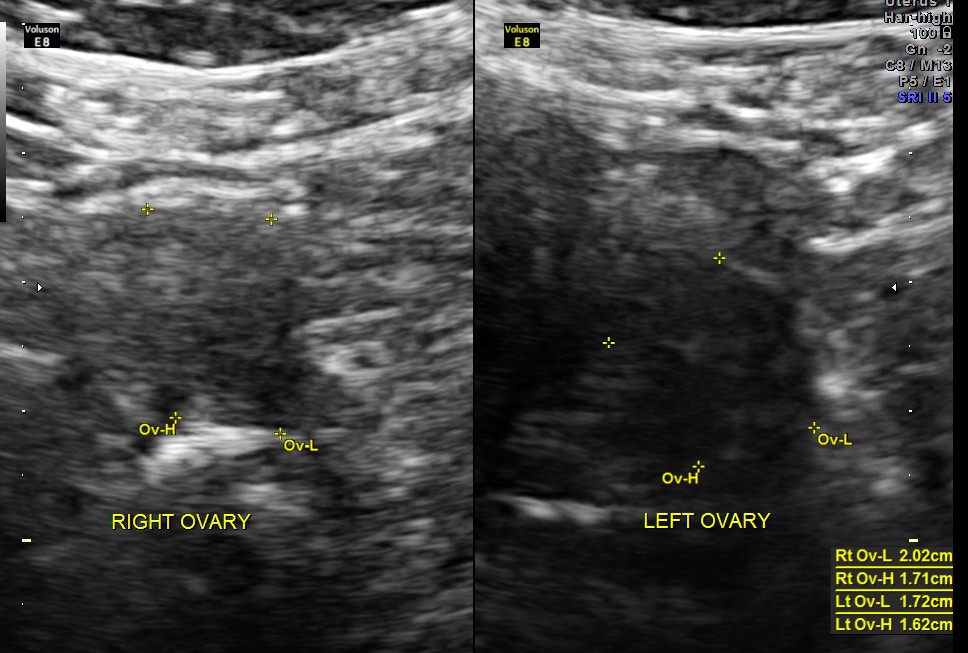

The ovaries were normal in appearance.